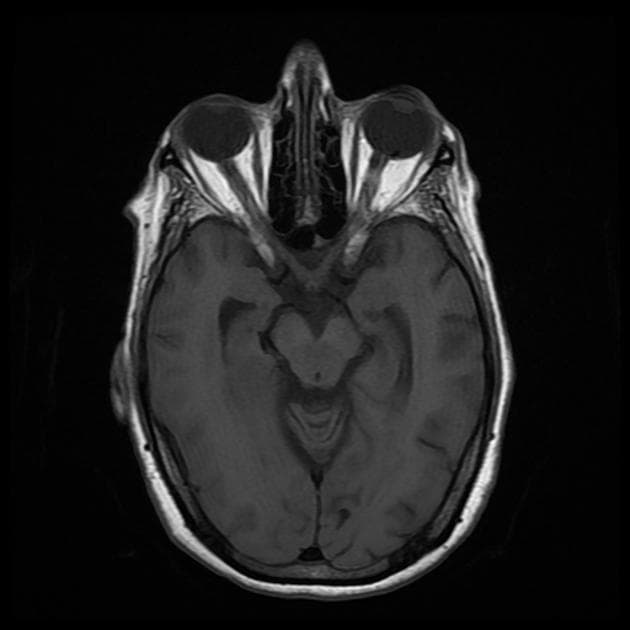

Thấy dày niêm mạc (mucosal thickening) các xoang cạnh mũi (paranasal sinuses).

Có tích tụ dịch (fluid accumulation) hai bên ở xoang hàm (maxillary sinuses) và xoang chũm (mastoid sinuses).

Ngoài ra, còn quan sát thấy hố yên rỗng (empty sella) và hốc Verga (cavum vergae).